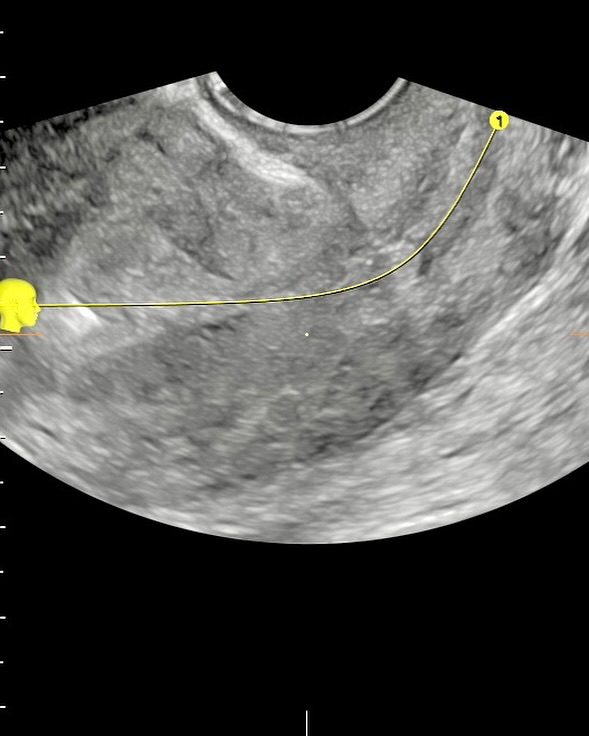

A ultrassonografia em três dimensões (3D) revolucionou a forma como avaliamos o útero e seu interior. Sua capacidade de gerar imagens volumétricas permite uma análise detalhada da cavidade endometrial, com cortes multiplanares que ampliam nossa percepção anatômica e funcional.

-  Quando falamos em dispositivo intrauterino (DIU), a avaliação 3D é especialmente útil. A reconstrução volumétrica permite verificar com precisão o posicionamento do DIU, identificando deslocamentos, inserções parciais ou até perfurações, muitas vezes imperceptíveis em exames bidimensionais convencionais.